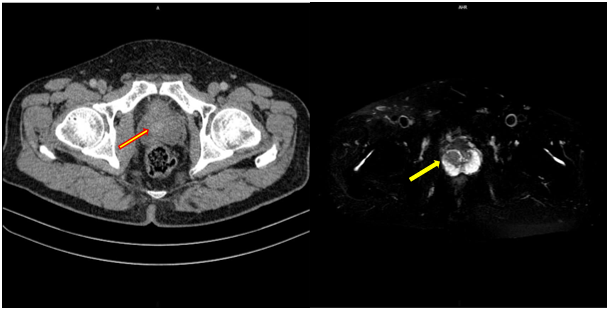

ĐAU TRONG UNG THƯ DI CĂN XƯƠNG

Hệ xương là vị trí phổ biến thứ ba cho di căn ung thư, chỉ sau phổi và gan. Nhiều bệnh lý ung bướu như ung thư vú, tuyến tiền liệt, phổi và thận, có khuynh hướng di căn mạnh mẽ đến xương, gây đau, tăng canxi máu, gãy xương bệnh lý, chèn ép...